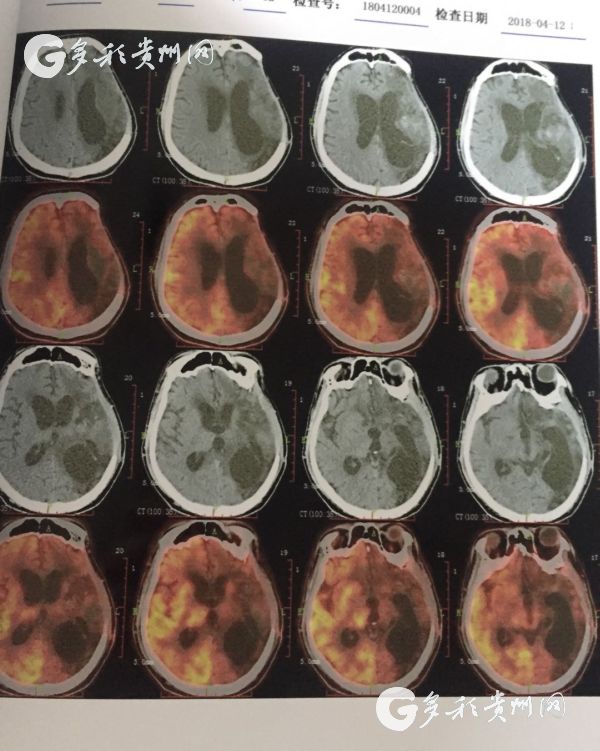

医院提供的患者脑部CT照

据了解,该患者是一位30岁男性,曾因脑出血进行过开颅手术,但术后并发症使病情加重,最后导致长期昏迷,家人最终将其送往77779193永利官网附属医院进行治疗。